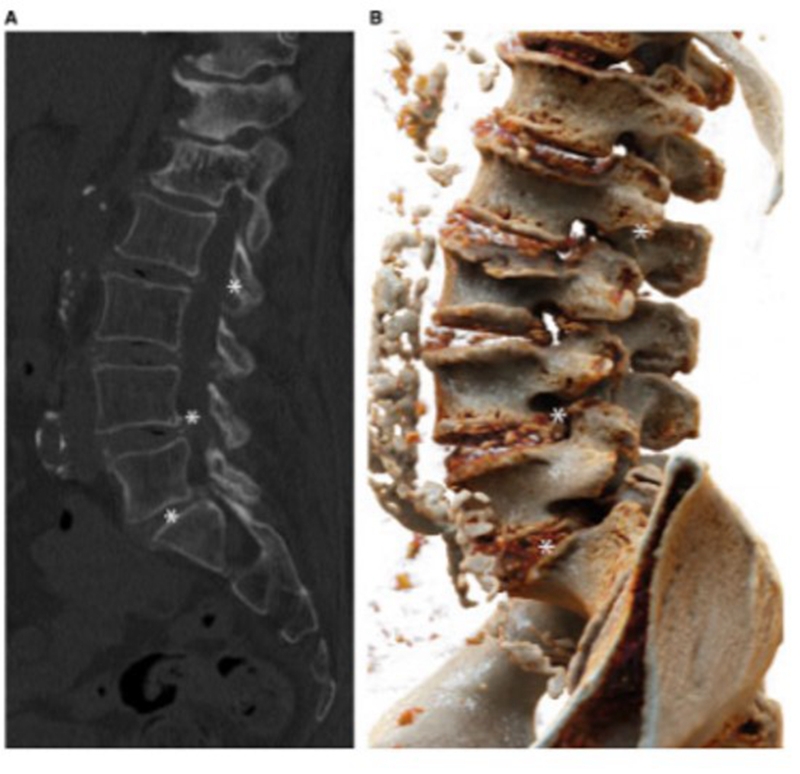

图1.受累部位呈点状、线状或斑片状钙化影(受累部位钙化所致),以及受累关节间隙间隙变窄,并可伴骨赘形成

创伤引起的腰椎焦磷酸钙沉积病

胸椎(A)和腰椎(B)脊柱MR图像显示C7-T1以及T1-2和T9-12椎间盘内有一些强化。从T9到T12也有腹侧硬膜外强化